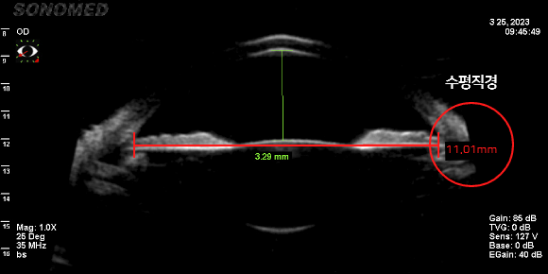

정확한 안구공간 측정

렌즈가 삽입될 공간이 충분한지 안구 공간 측정이 정확히 이루어져야 수술 가능 여부, 렌즈 사이즈,

렌즈 회전율을 최소화할 수 있는 렌즈 삽입 위치가 결정됩니다.

평균적으로 수직 직경이 수평 직경보다 길기 때문에 수직형 V-토릭 ICL은 넓은 공간에 여유 있는 사이즈의 렌즈가 삽입되어

렌즈 주변부의 접촉이 없어 렌즈삽입술의 부작용을 방어하고 안정성이 높습니다.

• 수평 안구 공간 측정 (11.01mm)

• 수평 안구 공간 측정 (11.22mm)

수직 직경 공간이 더 넓음